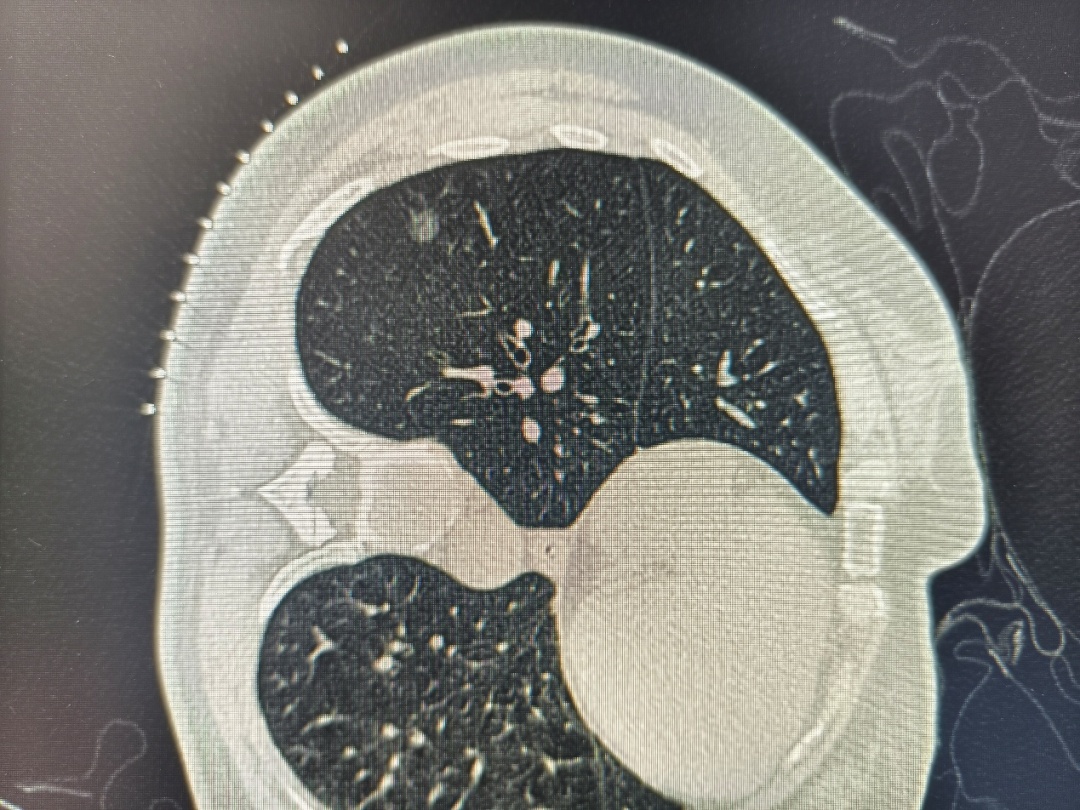

1. 影像观察“以貌取结”

大小:

结节越大,恶性风险越高。≤5mm的微小结节大多良性。

长相:

边缘光滑的常为良性;边缘有“毛刺”、分叶或胸膜牵拉的需警惕。

质地:

纯磨玻璃结节多为良性或极早期癌变;混合型磨玻璃结节若实性成分增多,风险上升。

纯磨玻璃肺结节

混合性肺磨玻璃结节

实性肺结节